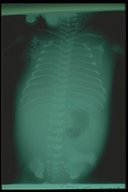

Chest X-ray of a "hydrops fetalis" baby soon after birth. The baby was prenatally diagnosed of bilateral chylothorax. Haziness were noted over both lung fields.

Immediate aspiration and intercostal drainage of both pleural spaces revealed milky fluid